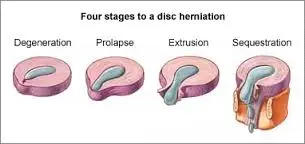

Disc herniations, or disc bulges occur when the disc that is found between vertebrae in the spine is damaged. Most of the time the damage occurs in stages.

Here are the four stages of a disc herniation or disc bulge:

- Disc Bulge

- Disc Prolapse

- Disc Extrusion

- Disc Sequestration

Think of the disc as a flat hard onion with strawberry jelly inside. The jelly is the nucleus while the onion layers form circular layers of hard cartilage called the annulus.

Disc Bulge

If you were to damage the annulus (onion) enough the disc gets to a point that when you bend forward, you pinch the front of the onion so it starts to bulge the onion at the back by pushing the nucleus (jelly) backwards.

This is called a disc bulge. For most of you, there is no pain but for some of you, there can be considerable lower back pain and even sciatica from this small disc bulge.

Disc Protrusion

A disc protrusion is like a disc bulge that comes out even more in one focused spot. The disc pushes out as if you had your finger inside a balloon and pushed out.

Most of the layers of the onion (annulus) have been damaged but the jelly (nucleus) is under considerable pressure. The jelly (nucleus) squeezes through the layers of the annulus (onion) with the few intact layers of the onion (annulus) and the PLL (posterior longitudinal ligament) holding the jelly from spilling out. The disc is still contained by the annulus and PLL ligament. ie the balloon hasn’t popped.

Disc Protrusions usually cause quite a bit of lower back pain and often times sciatica. Many of you, with disc protrusions, on the other hand, have absolutely no pain. There is no clear reason. A study found that 40% of people with no pain whatsoever had disc protrusion confirmed by MRI (Magnetic Resonance Imaging Machine) [1]

Disc Extrusion

Disc Extrusion is a disc bulge so large that it breaks through the last layers of the onion (annulus) and the PLL ligament pushing into the area of the spinal cord. ie. The balloon has popped. If you have an extrusion you likely have a tremendous amount of pain leg pain and usually some lower back pain.

Disc Sequestration

Disc sequestration occurs when a piece of your jelly (nucleus) that breaks through the onion (annulus) and the PLL ligament has now broken off and moved away further into the spinal cord area. When you have a disc sequestration you have a tremendous amount of leg pain and some lower back pain.